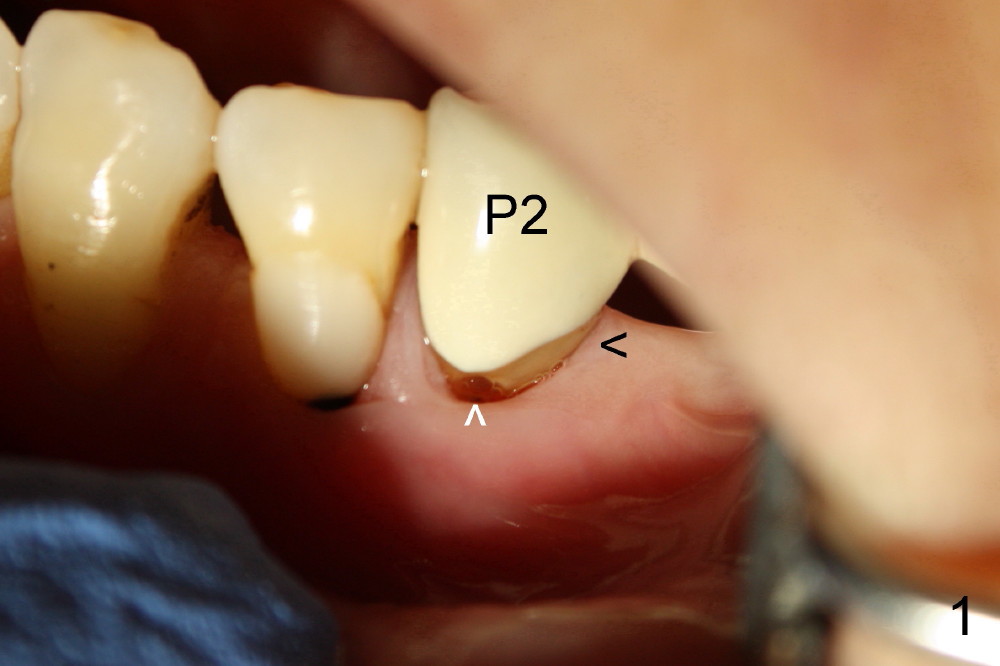

我们先修复颈部缺损(图三黑箭头),然后完成根管治疗,最后用树脂封闭牙合面开口(白箭头),图四显示根管治疗完毕;第一(P1)第二(P2)双尖牙牙根很接近,做植牙有难度。